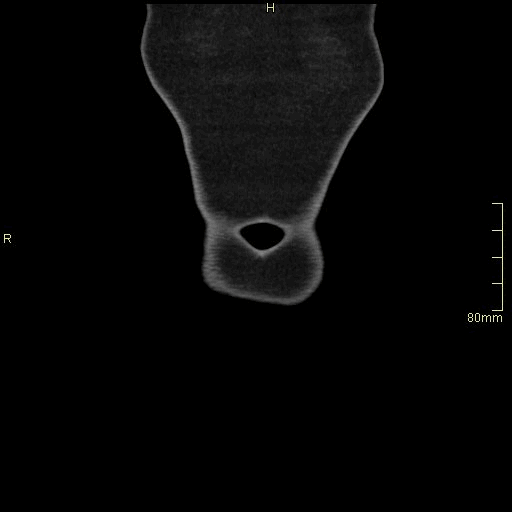

CT Urogram No Contrast (Coronal)